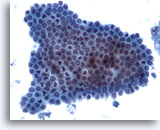

画像 5

肝FNA – 良性胆管細胞

良性胆管細胞の集塊。蜂巣状に配列し、均一な小型の核がみられます。

20倍

画像 5

肝FNA – 良性胆管細胞

良性胆管細胞の集塊。蜂巣状に配列し、均一な小型の核がみられます。

20倍